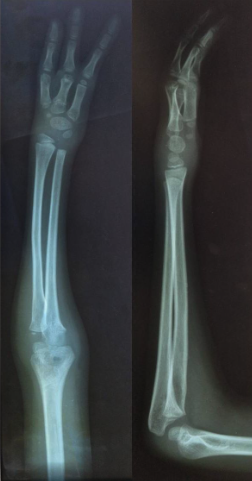

The third patient was a 12-year-old boy with type 1 deficiency (ulnar-deficient hand without radial or central hand anomalies). Clinically, there was an abduction deformity and camptodactyly of the small finger of the affected right hand. A wide web space between the ring and little fingers extending to the proximal interphalangeal joint level was evident. There was hypoplasia of the right small and ring finger rays. Radiographs showed a distal radial metaphyseal fracture, isolated complete longitudinal absence of the fifth metacarpal, hypertrophy of the fourth metacarpal, and lunate-triquetral coalition; the little finger shared the distal joint surface of the fourth metacarpal with the ring finger (Figure 3).

The fourth patient was a 23-year-old man with type 2A deficiency (absence of the ulnar styloid in an otherwise normal ulna and ulnar deficient hand with central hand anomalies). Clinically, the affected left hand had 3 fingers (oligodactyly with thumb). Despite the cosmetic problems, the patient had a functional extremity and a stable wrist. There was camptodactyly of the ulnar finger. The thenar muscles were well formed, while the muscle bulk of the right hypothenar eminence was not evident. Radiographs showed aplasia of the ulnar styloid process and a hypertrophied central metacarpal. The latter indicated that the central finger ray was present as symmetrical polysyndactyly rather than as a fusion of the middle and index finger rays and indicated the diagnosis of a central ray aplasia. The carpal bones were fewer either due to congenital absence or carpal coalition. Considering the abnormalities of the carpal bones, the missing ulnar digit was presumed to be the fifth finger. The diameter of the ulna was normal, both the radius and ulna were straight, and there was no abnormal deviation of the wrist and hand (Figure 4).